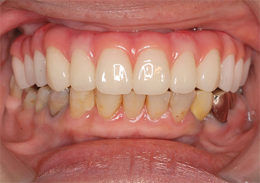

上顎のALL-ON-4②(ノーベルクリニシャンを使用したフラップレス術式)

フラップレス術式は、メスを使用しない無切開手術(フラップレス術式)です。

手術前の精密検査(CT撮影)によって顎骨の状態を正確に把握し、3Dコンピューターシミュレーション(ノーベルクリニシャン)による診断でインプラント埋入部位の詳細な治療計画が立てられるため、一般的なインプラント手術で必要となる切開・剥離・縫合のステップが省略できるため、短時間での手術が可能になります。

そして、出血もほとんどなく術後の腫れや痛みを軽減できるため、患者様の身体的負担を軽減できる低侵襲な最新のインプラント術式です。

-

- 主訴

- 歯周病で歯がグラグラするので噛めない

- 治療内容

- 上顎に残存していた歯を抜歯。歯肉の治癒後にフラップレス手術にてインプラント埋入を行い、その場で準備してあった上顎上部構造を仮歯として、ねじ固定式で装着

- 治療費用

- 上顎ALL-ON-4:4,000,000円(税別)

- 治療期間

- 6ヶ月